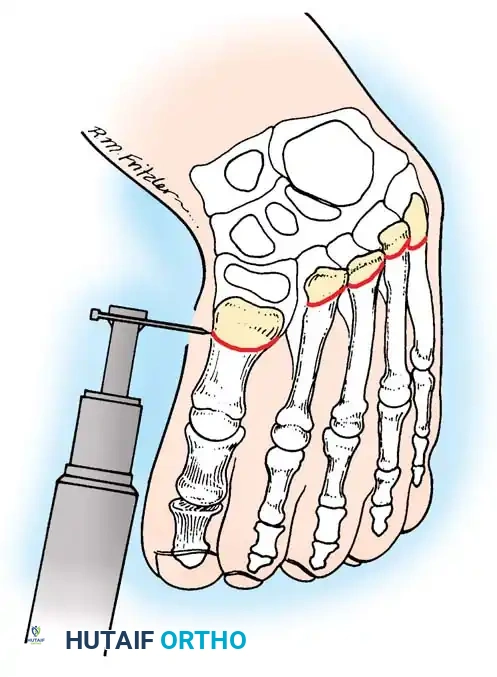

For children 4 years of age and older presenting with residual, rigid metatarsus adductus, multiple metatarsal osteotomies are the procedure of choice. Berman and Gartland described dome-shaped osteotomies at the bases of all five metatarsals. The dome shape provides inherent stability and allows for multiplanar correction without shortening the metatarsals.

- Osteotomy: Using a small power drill or a specialized crescentic oscillating saw blade, create a dome-shaped osteotomy in each metatarsal base.

- Crucial Detail: The apex of the dome must point proximally.

- Pitfall Avoidance: Strictly avoid the physis at the base of the first metatarsal, which is located proximally.

Fig. 9: Berman and Gartland technique. A dome-shaped osteotomy is completed at the base of each metatarsal using a power drill or crescentic saw, with the apex directed proximally.